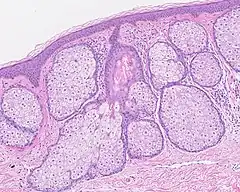

Les glandes sébacés ont une architecture acinaire (comme une grappe de raisin) et n'ont pas de lumières propre. Elles sont composés de sébocytes matures, dont la sécrétion est le résultat de leur mort par apoptose, ce qui revient à une sécrétion holocrine. Le remplacement des cellules est assuré par les cellules de la matrice reposant sur la membrane basale[5].L'annexe pilo-sébacée constituée du follicule pileux, des glandes sébacés et des muscles arrecteurs du poils, résulte d'une invagination épithéliale[4].

Annexe pilosébacée avec glandes sébacés s'abouchant à un follicule pileux.

Multiples glandes sébacés volumineuses réalisant une hyperplasie sébacée.

Multiples glandes sébacés s'abouchant à un follicule pileux.